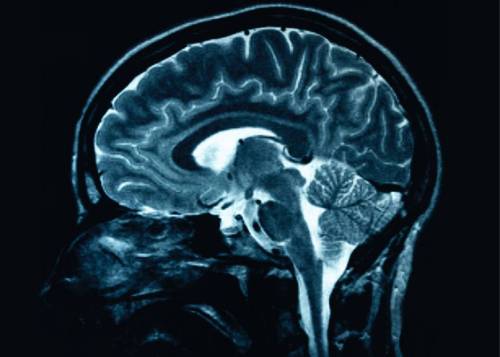

A study using neuroimaging led by Stony Brook University professor and lead author Lilianne R. Mujica-Parodi, PhD, and published in PNAS, reveals that neurobiological changes associated with aging can be seen at a much younger age than would be expected, in the late 40s. But the study also suggests that this process may be prevented or reversed based on dietary changes that involve minimizing the consumption of simple carbohydrates.

Even in younger adults, under age 50, dietary ketosis (whether achieved after one week of dietary change or 30 minutes after drinking ketones) increased overall brain activity and stabilized functional networks.